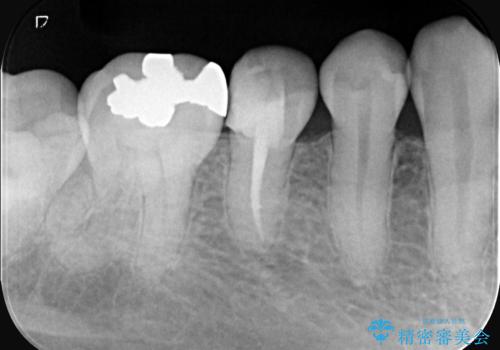

- 虫歯が大きく歯が欠けている状態でした。 そこに食べ物も詰まっている状態でした。

虫歯を除去後、精密根管治療を行い、オールセラミッククラウンで治療を行いました。

虫歯が大きく神経まで到達していました。将来根尖性歯周炎にならないよう徹底的に神経をとり洗浄したうえで被せ物をしています。